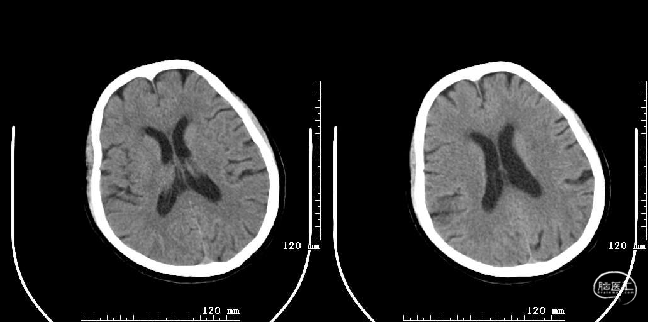

术后第二天复查头颅MRI

4月2日(术后10天)患者左肢无力及言语障碍较前好转,语言流利,双眼未见凝视,伸舌居中,示齿口角稍右歪,左侧鼻唇沟稍浅,四肢肌力V级。NIHSS评分1分(面瘫1分),mRS 1分。